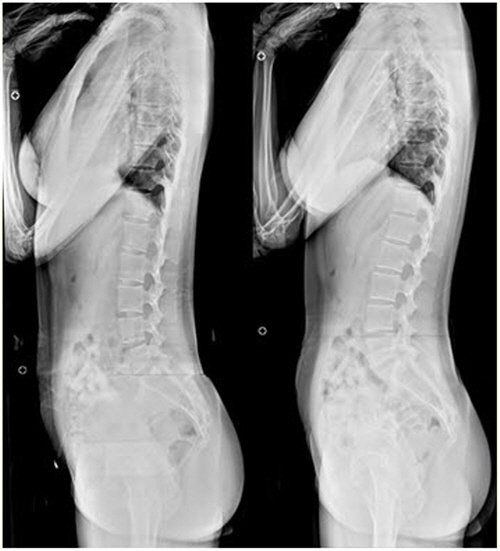

10. 운동 범위 감소

허리 디스크는 해당 부위의 운동 범위를 제한할 수 있습니다. 이러한 제한으로 인해 특정 동작을 수행하거나, 구부리거나, 편안하게 비틀기가 어려울 수 있습니다. 뻣뻣함과 유연성 감소는 운동 범위 감소와 관련된 일반적인 증상입니다.